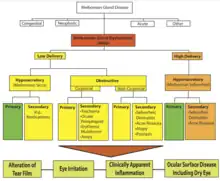

| Types | Low delivery (hyposecretory or obstructive) and High delivery. |

MGD can be classified based on gland secretion. MGD can be low delivery and high delivery. Low delivery is the most common form[5] and is classified in hyposecretory and obstructive. Hyposecretory implies low meibum secretion without terminal duct obstruction. This is associated with gland atrophy. Contact lens wear can lead to a decreased number of functional meibomian glands.[2] Obstructive MGD, where the terminal duct is obstructed, is the most common type of MGD. Obstructive MGD has been associated with age and acne treatment products with retinoids.[2] Obstructive MGD can be classified into noncicatricial and cicatricial. In noncicatricial, the terminal duct of meibomian glands are in their normal anatomic position. In cicatricial, they are dragged posteriorly into the mucosa.[2]

High delivery implies an increased release of meibum into the tear surface. This has been associated with seborrheic dermatitis.[2]